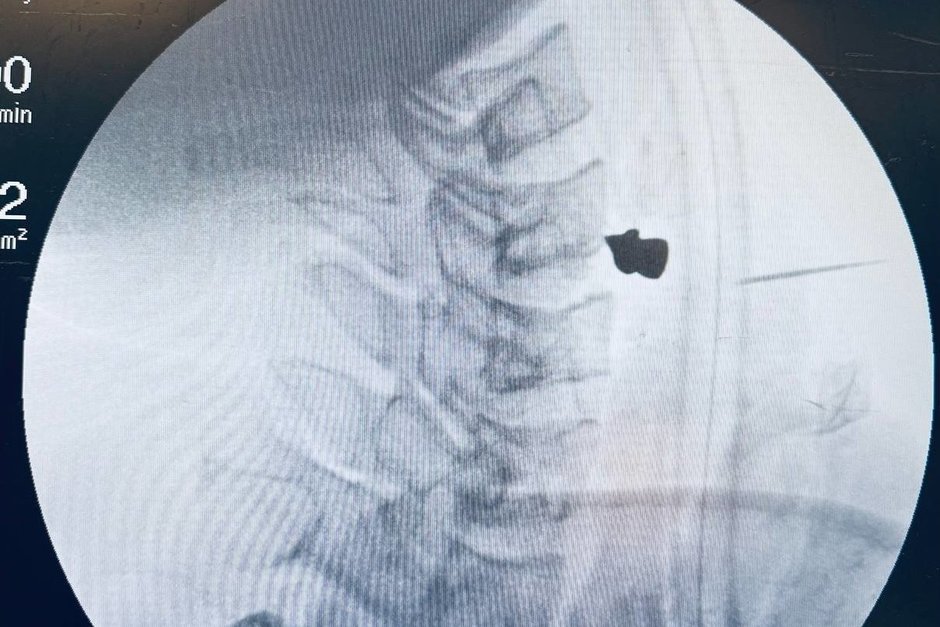

При поступлении мужчина испытывал трудности с глотанием и речью. Проведенная компьютерная томография показала, что пуля прошла через шею и остановилась в позвоночнике, чудом обойдя все жизненно важные сосуды и органы.

Экстренная операция, занявшая всего 20 минут, была проведена заведующим ЛОР-отделением Маратом Гиляловым совместно с заведующим отделением нейрохирургии №2 Георгием Майковым. Врачи аккуратно извлекли пулю и зашили рану.